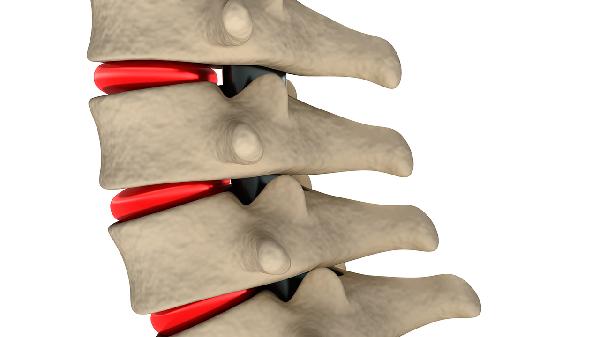

若为不稳定性骨折或伴有脊髓损伤,一个月内禁止负重活动。这类骨折多由高处坠落、车祸等高能量损伤导致,常合并椎体爆裂、椎弓根断裂或椎管占位。过早下床可能导致骨折移位加重,甚至造成永久性神经损伤。患者需严格卧床6-8周,通过轴向翻身预防压疮,定期复查X线或CT观察骨痂形成情况。待影像学显示骨折线模糊、脊柱序列稳定后,方可在康复师指导下开始渐进式负重训练。